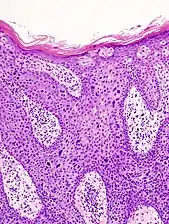

In situ disease

Bowen's disease is essentially equivalent to and used interchangeably with cSCC in situ, when not having invaded through the basement membrane.[12] Depending on source, it is classified as precancerous[13] or cSCC in situ (technically cancerous but non-invasive).[47][48] In cSCC in situ (Bowen's disease), atypical squamous cells proliferate through the whole thickness of the epidermis.[12] The entire tumor is confined to the epidermis and does not invade into the dermis.[12] The cells are often highly atypical under the microscope, and may in fact look more unusual than the cells of some invasive squamous-cell carcinomas.[12]

cSCC in situ, high magnification, demonstrating an intact basement membrane.[12]